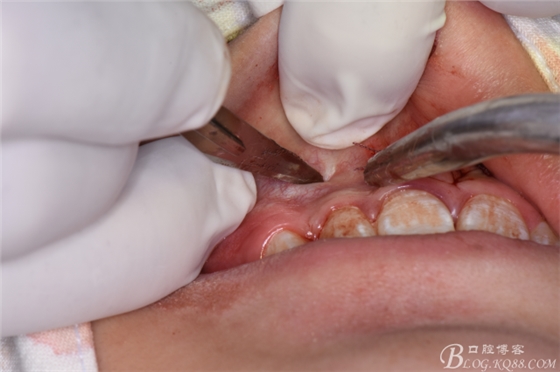

圖20. 在12、13根尖所對應(yīng)的前廳溝處做第二個弧形切口

圖21.一定要切透粘骨膜。

圖22.翻瓣、暴露骨面